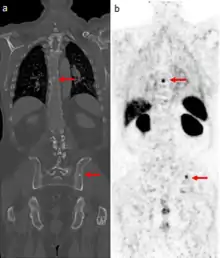

CT scan (left) and gallium PSMA PET scan (right) of patient with prostate cancer metastases in the bones

The positron emitting isotope, 68Ga, can be used to target prostate-specific membrane antigen (PSMA), a protein which is present in prostate cancer cells. The technique has been shown to improve detection of metastatic disease compared to MRI or CT scans.[27]